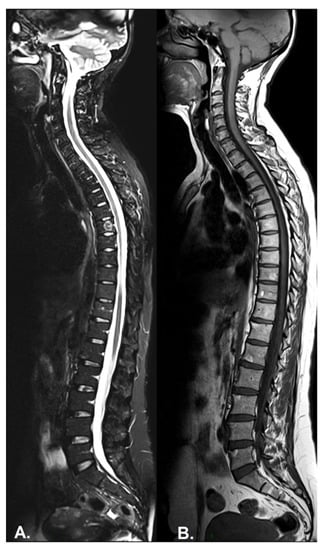

3.2. Imaging Protocols

3.2.1. Axial PsA

- Sagittal T1-weighted (T1w) sequences—best for the characterization of fat content or to assess structural bone lesions.

- Sagittal T2-weighted Fat-Sat fast spin echo sequences and short tau inversion recovery (STIR) sequences (short tau inversion recovery) sequences in two planes for water content evaluation/BMO.

- For a better assessment of the costovertebral and costotransverse joints and the facet joints, coronal sequences can be added to the protocol [58].

- Sagittal T1w Fat-Sat sequences with gadolinium enhancement—used for the detection of osteitis; increased perfusion; rarely used, in cases of doubt and high suspicion, to differentiate exudate from synovitis or to assess the activity of bone erosions [59].